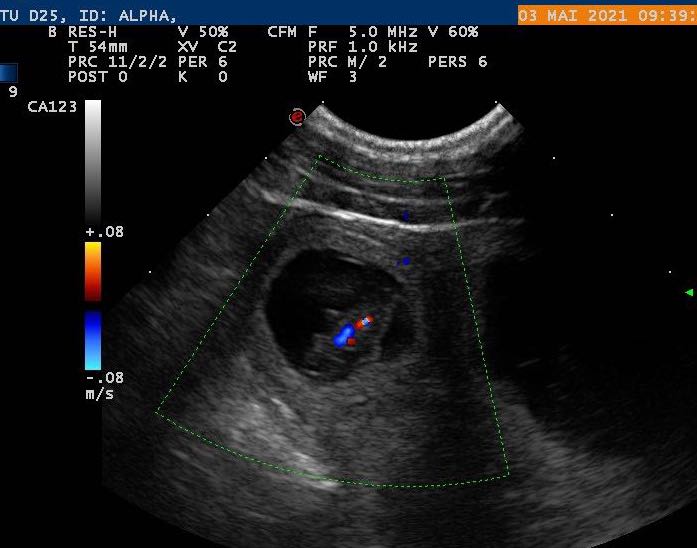

Update 3.5.2021: Heute waren wir beim Ultraschall uuund..Alpha ist trächtig! Wir erwarten unsere H-Horde also um den 10.6. :-).